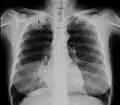

Een pancoasttumor (het hebben ervan wordt ook wel het pancoastsyndroom of sulcus-superior-syndroom genoemd) is een tumor die is gelokaliseerd in de longtop. Door de lokalisatie kan deze de werking van bepaalde zenuwen die het gelaat verzorgen in functie verstoren. Een veelvoorkomende aanleiding om hiernaar op zoek te gaan is het syndroom van Horner.